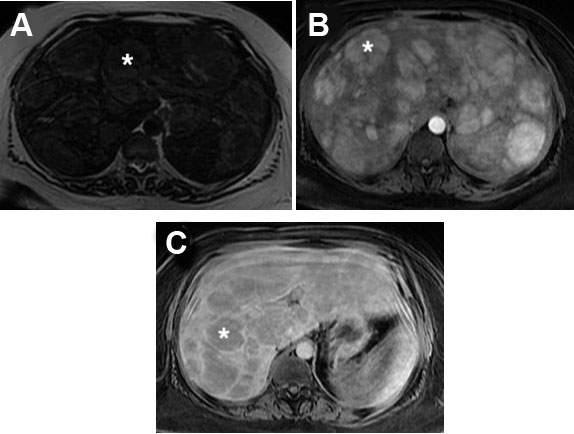

A 33-year-old black female with a past medical history of seizures, hypertension, type-2 diabetes, cognitive impairment, and neuropathy resulting in complete loss of ambulation was referred to our institution for radiologic evaluation following an abnormal liver function test (alkaline phosphatase (ALP) 1193; alanine transaminase/aspartate transaminase (ALT/AST) were normal at 16/16 U/L), microcytic anemia, and a vitamin B12 deficiency. No alcohol, drug, tobacco use, or family history of liver disease were noted. On physical exam, jaundice and abdominal pain were absent; chronic fatigue had been present for several months. Abdominal ultrasound (Figure 1A and Figure 1B) revealed hepatomegaly that exceeded 23 cm, with multiple heterogenous masses in both lobes of the liver hyperechoic to the surrounding parenchyma; further evaluation with contrast-enhanced CT (Figure 2A, Figure 2B, Figure 2C) revealed enhancement of approximately 100 lesions throughout both liver lobes, the largest measuring 5–6 cm. The liver parenchyma had a uniform density without pathologic enhancement and a normal gallbladder without evidence of biliary dilation. Magnetic resonance imaging (MRI) (Figure 3A, Figure 3B, Figure 3C) shows numerous T2 hyperintense hepatic lesions, which enhanced during the arterial phase with intravenous (IV) gadolinium. To rule out a hyper-vascular primary malignancy or vascular metastasis, a CT-guided percutaneous biopsy of the liver was performed. Pathology identified mild macro-vesicular steatosis and marked sinusoidal dilation (Figure 4A, Figure 4B, Figure 4C), consistent with peliosis hepatis and mild macro-vesicular steatosis of the liver. Occult bleeding of the upper and lower gastrointestinal tract (GI) tract was ruled out; the anemia was treated with Vitamin B12 injections and IV iron transfusions. After two years of follow-up, the anemia persisted; testing revealed alfa-thalassemia minor. Radiographic follow-ups noted stable lesions; the patient has remained asymptomatic three-years post-diagnosis. Interestingly, however, the patient’s lab values have continued to show elevated ALP levels that vary between 1200 and 1700 IU/L, while the ALT/AST values have remained normal.

Figure 3: Magnetic resonance imaging of the liver. (A) T2 sequence demonstrates numerous hepatic lesions (*) that are mildyT2 hyperintense. (B) These lesions (*) enhance avidly in the arterial phase with intravenous gadolinium. (C) Liver lesions (*) are relatively hypointense in the venous phase sequence.

Magnetic resonance imaging (MRI) was a commonly utilized imaging modality (40.0%; n=25) with MRI T1-weighted images appearing hypointense with an enhancement that progresses centrifugally; cavities display a rim of enhancement with hematoma [17],[18],[26],[35]. T2-weighted MRI images appear hyperintense to the parenchyma with multiple foci of high signal, consistent with what was seen in our patient using Gadolinium contrast enhancement (Figure 3) [16],[17],[18],[26].